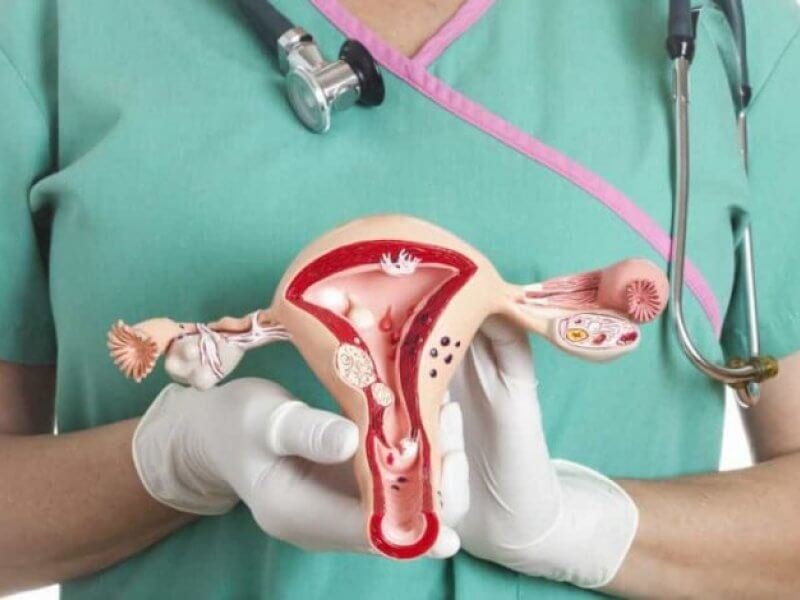

Gizlilik Esaslı Kürtaj

Kürtaj İşlemi

Hızlı ve Güvenli Kürtaj işlemi (Gizlilik Garantisi)

18 yaşını geçmiş her kadın gebeliğinin 10. haftasına kadar hem hastanelerde hem de kliniklerde kürtaj yaptırabilir. Eğer evli ise eşinin de onayının alınması gerekli bir prosedürdür. 18 yaşının altındaki bireylerin kürtaj yaptırabilmeleri için ebeveyn iznine ve savcılık iznine gerek duyulur. Bu prosedürlerin yerine getirilmesi durumunda kürtaj yapılabilir.

Kürtaj yüzyıllardır dünyanın her yerinde uygulanan bir yöntem ve bir haktır. Kürtajın yasal olduğu ve yasal olmadığı ülkeler arasındaki kürtaj yapılma oranları arasındaki fark çok azdır. Bu da demek oluyor ki kürtajın yasal olmadığı ülkelerde kürtaj yapılmaya devam ediyor ancak bu işlem güvenli olmayan, denetlenmeyen şartlar altında yapılıyor.